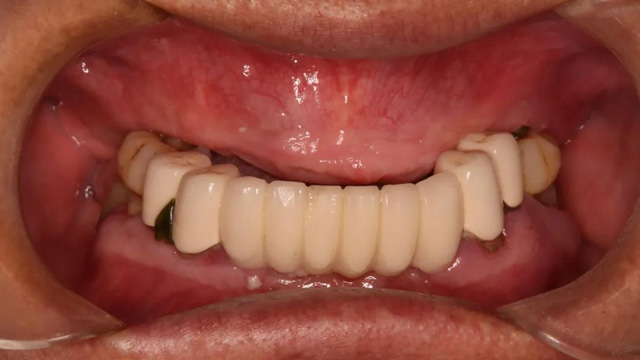

王先生全口種植后戴冠

王先生正式戴牙后